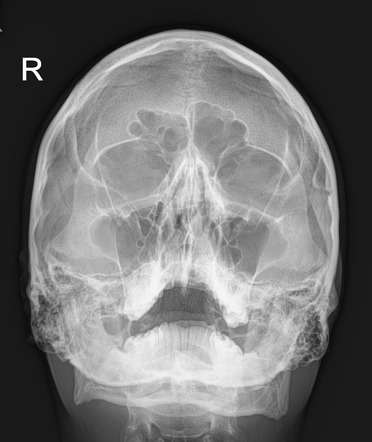

What is the Waters or Occipito-Menton projection?

canthomeatal plane forms 37 angle with image receptor, pt faces receptor

What does the waters projection give insight to?

Sinuses, cheek bones, septum and mandible

What is the towne's veiw of the skull?

The anterior-posterior view where pt facing away from receptor and chin tilted down -30 degrees